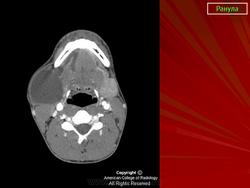

Ранула, или слизистая киста подъязычной железы.

Ранула — слизистая киста дна полости рта больших размеров. Как и другие слизистые кисты, ранула образуется в результате скопления слюны в подслизистой ткани при повреждении протока слюнной железы. В большинстве случаев причиной образования ранулы бывает повреждение главного выводного протока подъязычной (бартолинов проток) или подчелюстной (вартонов проток) железы, реже — повреждение протоков добавочных слюнных желёз дна полости рта. Обычно ранулу выявляют улиц старше 40 лет, её одинаково часто встречают у мужчин и у женщин.

Ранулы бывают двух типов: при более частом, поверхностном, типе она локализуется поверхностно на дне полости рта и имеет мягкую консистенцию, при втором, или «ныряющем», типе она располагается под челюстно-подъязычной мышцей и вызывает припухлость в подбородочной области. Поверхностная ранула просвечивает и имеет характерный синеватый оттенок, располагается на одной стороне, флюктуирует. По мере роста ранулы слизистая оболочка над ней растягивается, истончается, становится напряжённой. В отличие от дермоидной кисты после надавливания на ранулу на ней не остаётся ямки. Разрыв ранулы приводит к истечению её содержимого. При больших размерах ранула может занимать все дно полости рта, приподнимая язык и ограничивая его движения. Это вызывает нарушение жевания, глотания, речь.

Ранулу следует дифференцировать от других опухолевидных образований дна полости рта, таких как дермоидная киста и опухоли слюнных желёз (например, мукоэпидермоидный рак подчелюстной железы). При необходимости для уточнения диагноза выполняют сиалографию и биопсию. Лечение ранулы заключается в хирургическом иссечении или марсупиализации (операция Парча), при которой кисту частично иссекают и края её стенки подшивают к краям операционной раны. Вскрытие и дренирование ранулы — неэффективный метод лечения, так как после этого в её полости вновь скапливается жидкость. Недостаточно тщательно выполненная операция приводит к рецидиву как при поверхностном, так и при ныряющем типе ранулы. В таких случаях обычно прибегают к удалению слюнной железы.